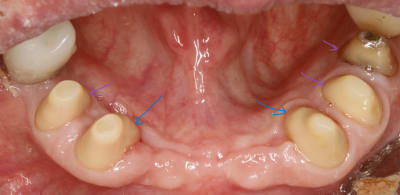

ici , on doit faire un bridge canine canine .les autres dents sont juste des piliers accessoires .

dejà , le bridge canine +accessoires par sa forme de fer à cheval est auto stable puisque les forces principales viennent d en haut et de devant .

les canines etant les plus costaudes , on va donc essayer de ne pas trop les fracasser et les choisir comme axe d insertion . ce sera donc notre axe de taille directeur . cet axe etant bien sur l axe moyen (ou commun) entre les deux .

donc on commence par tailler les canines en mettant de dépouille .

devant ( en vestibulaire ) on a vu que c etait auto stable , à condition bien sur de laisser la place au montage des dents . donc la courbure de devant dépend de la forme cingulaire des dents du haut .eh oui :-)

alors maintenant derrière c est diffèrent , avec la langue , ce n est pas du tout auto stable , et vu que devant c est assez incliné , il va falloir trouver de la rétention . et y en a pas beaucoup et elle se trouve juste au depart de la dent . elle est si précieuse qu une fois taillée , on y reviendra plus jamais .

ce sera notre axe de rétention de référence pour tout le bridge .

et on ne peut pas dire qu il y ait de la conicité entre les deux .

voir les traits bleus sur la photo , sauf si comme dans mission impossible , elle disparait .:-)